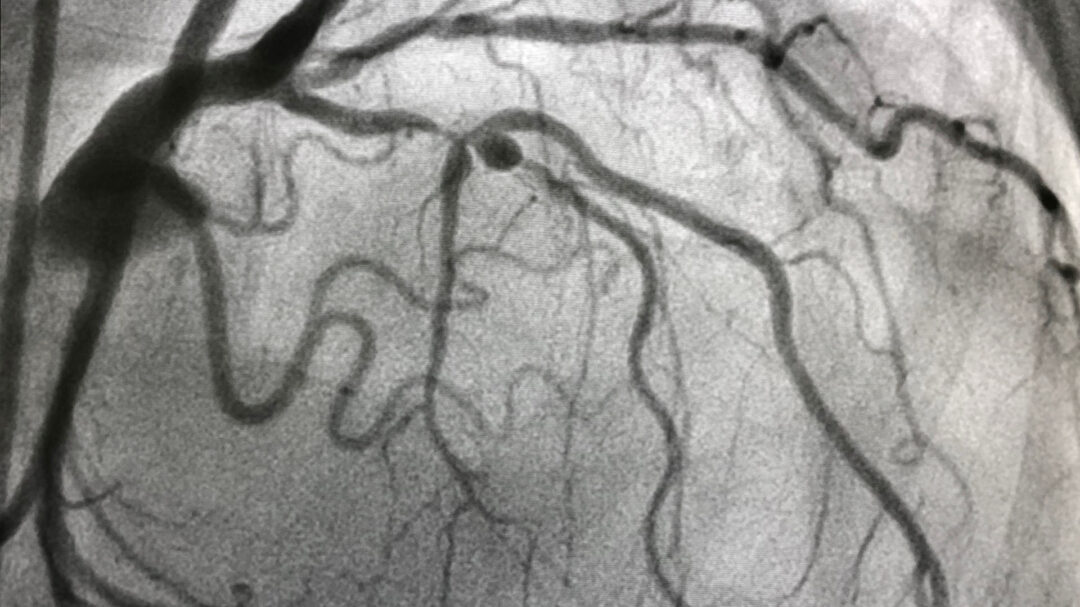

Σύμφωνα με τους ειδικούς ανατόμους του 17ου αιώνα, οι αρτηρίες που αιματώνουν την καρδιά την περιβάλλουν σαν στεφάνι, γι’ αυτό και είναι γνωστές ως στεφανιαίες αρτηρίες. Ξεκινούν από την αορτή, τη μεγαλύτερη αρτηρία του σώματος, και φέρονται στον μυ της καρδιάς, τροφοδοτώντας αυτό το όργανο με αίμα και οξυγόνο. Τα υγιή μικρά παιδιά έχουν εύκαμπτες, ελαστικές στεφανιαίες αρτηρίες. Με την πάροδο του χρόνου, οι αρτηρίες της καρδιάς γίνονται σταδιακά πιο δύσκαμπτες και πιο στενές, καθώς στο εσωτερικό των τοιχωμάτων τους αναπτύσσεται αθηρωματική πλάκα, η οποία σχηματίζεται από χοληστερόλη και άλλες ουσίες. Η κατάσταση αυτή, που ονομάζεται στεφανιαία νόσος, ευθύνεται για τις καρδιακές προσβολές, που στις ΗΠΑ συμβαίνουν μία σχεδόν κάθε 40 δευτερόλεπτα.

Κάθε χρόνο, περίπου 480.000 Αμερικανοί υποβάλλονται σε αγγειοπλαστική, μια διαδικασία που αποσκοπεί στη διεύρυνση μιας στεφανιαίας αρτηρίας που εμφανίζει στένωση. Συνήθως πραγματοποιείται με χρήση ενός μικρού σωληνίσκου από μεταλλικό πλέγμα (stent), ο οποίος τοποθετείται στο εσωτερικό της αρτηρίας ώστε να την κρατάει ανοιχτή. Γύρω στα δύο τρίτα αυτών των επεμβάσεων πραγματοποιούνται σε άτομα που έχουν εμφανίσει καρδιακή προσβολή ή ασταθή στηθάγχη. «Στα άτομα αυτά, η διάνοιξη των αρτηριών με στένωση μπορεί να τους σώσει τη ζωή», δηλώνει ο δρ Yeh, ο οποίος είναι επίσης διευθυντής στο Smith Center for Outcomes Research in Cardiology στο Beth Israel Deaconess Medical Center. Η τοποθέτηση ενός stent μπορεί να αποκαταστήσει τη ροή αίματος (και οξυγόνου) στην καρδιά μέσα σε περίπου 20 λεπτά – τόσος είναι ο μέσος χρόνος διάρκειας της επέμβασης.